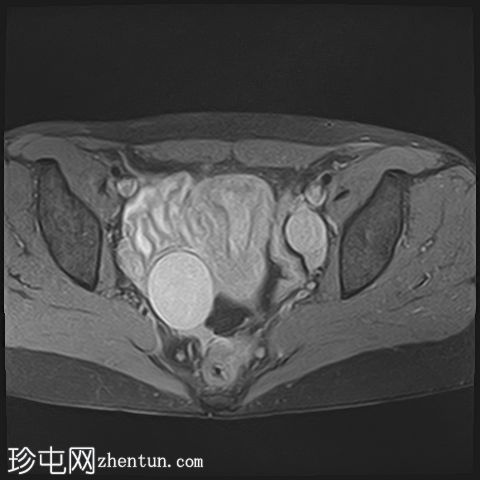

轴向

T1

已确诊3例卵巢囊肿:

右侧卵巢出血性囊肿,T1成像呈中等信号,T2成像呈高信号,伴有薄内部分隔

左侧卵巢出血性囊肿,信号特征与右侧囊肿相似

左侧单纯性卵巢旁囊肿,T1成像呈低信号,T2成像呈高信号

此外,所有囊肿均未显示弥散受限或实性成分强化。

所有囊肿均仅显示薄层外周壁强化。

道格拉斯囊右侧可见轻度积液。

本例卵巢囊肿呈中等 T1 信号,类似于肌肉信号,T2 信号高,伴有薄内隔和外周壁强化。但无内部强化或弥散受限。STIR 序列显示与 T2 一致的信号,无任何脂肪成分。该表现提示卵巢出血性囊肿处于早期或消退期。

此外,左侧卵巢旁囊肿外观简单,T1 信号低,T2 信号高。